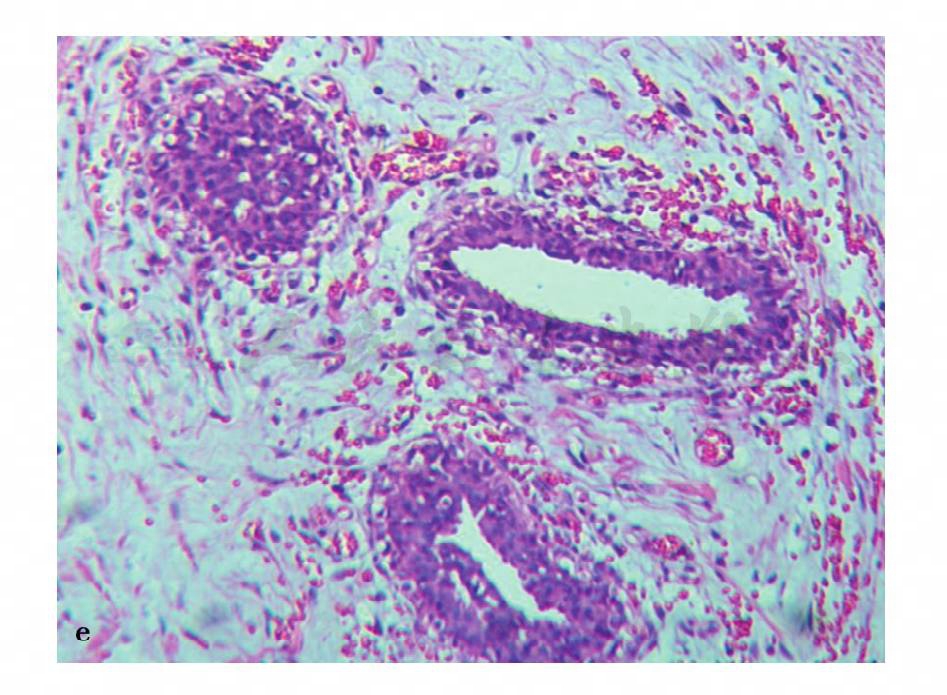

图23 e,病理结果:男性乳腺发育